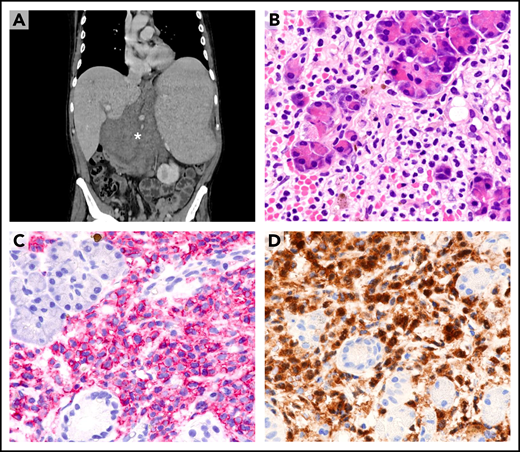

Dissemination of HCL to sites other than blood, marrow, and spleen (eg, lymph node or skin) is rare47 and usually occurs after multiple relapses (Figure 4A). Under these circumstances, only a paraffin-embedded biopsy sample is often available for diagnosis. Leukemic cells usually retain the typical HCL morphology (Figure 4B) and immunophenotype (eg, expression of B-cell antigens [Figure 4C] and ANXA13,4,48-50 [Figure 4D]). Expression of BRAF-V600E can be demonstrated by IHC,44-46 and its retention even in unusual sites further supports its clonal stability during the course of the disease.

Extramedullary involvement in refractory/relapsed HCL. (A) Computed tomography scan shows a large abdominal mass (asterisk), marked splenomegaly, and enlarged mediastinal lymph nodes (not shown). (B) Needle biopsy of the abdominal mass reveals infiltration of pancreatic glands by morphologically typical HCL cells with wide clear cytoplasm (hematoxylin-eosin; ×400). (C) HCL cells (red) strongly express the CD19 antigen (APAAP immunostaining, hematoxylin counterstaining; ×400). (D) HCL cells (brown) are also annexin-A1+ (immunoperoxidase staining; hematoxylin counterstaining; ×400). APAAP, alkaline phosphatase anti-alkaline phosphatase.